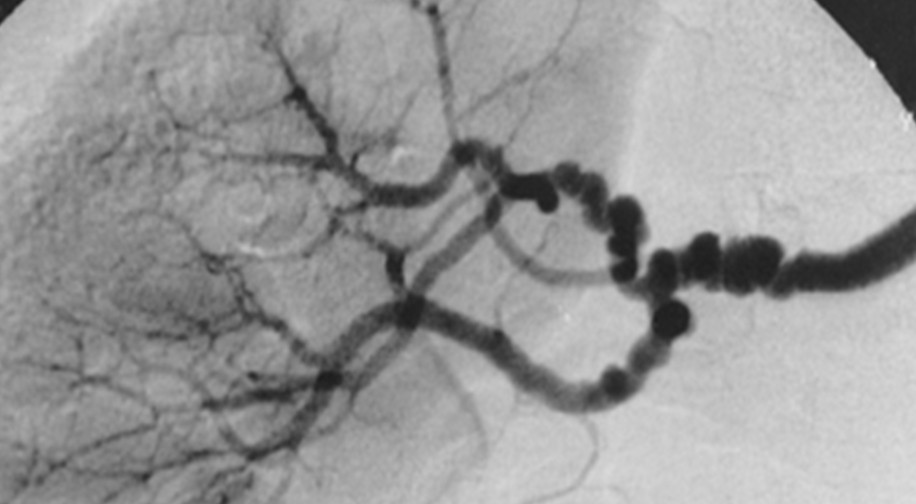

fibromuscular dysplasia

string of beads

commonly affects ICAs and verts

more common in females

slight incr risk TIA/stroke and dissection but often asymptomatic